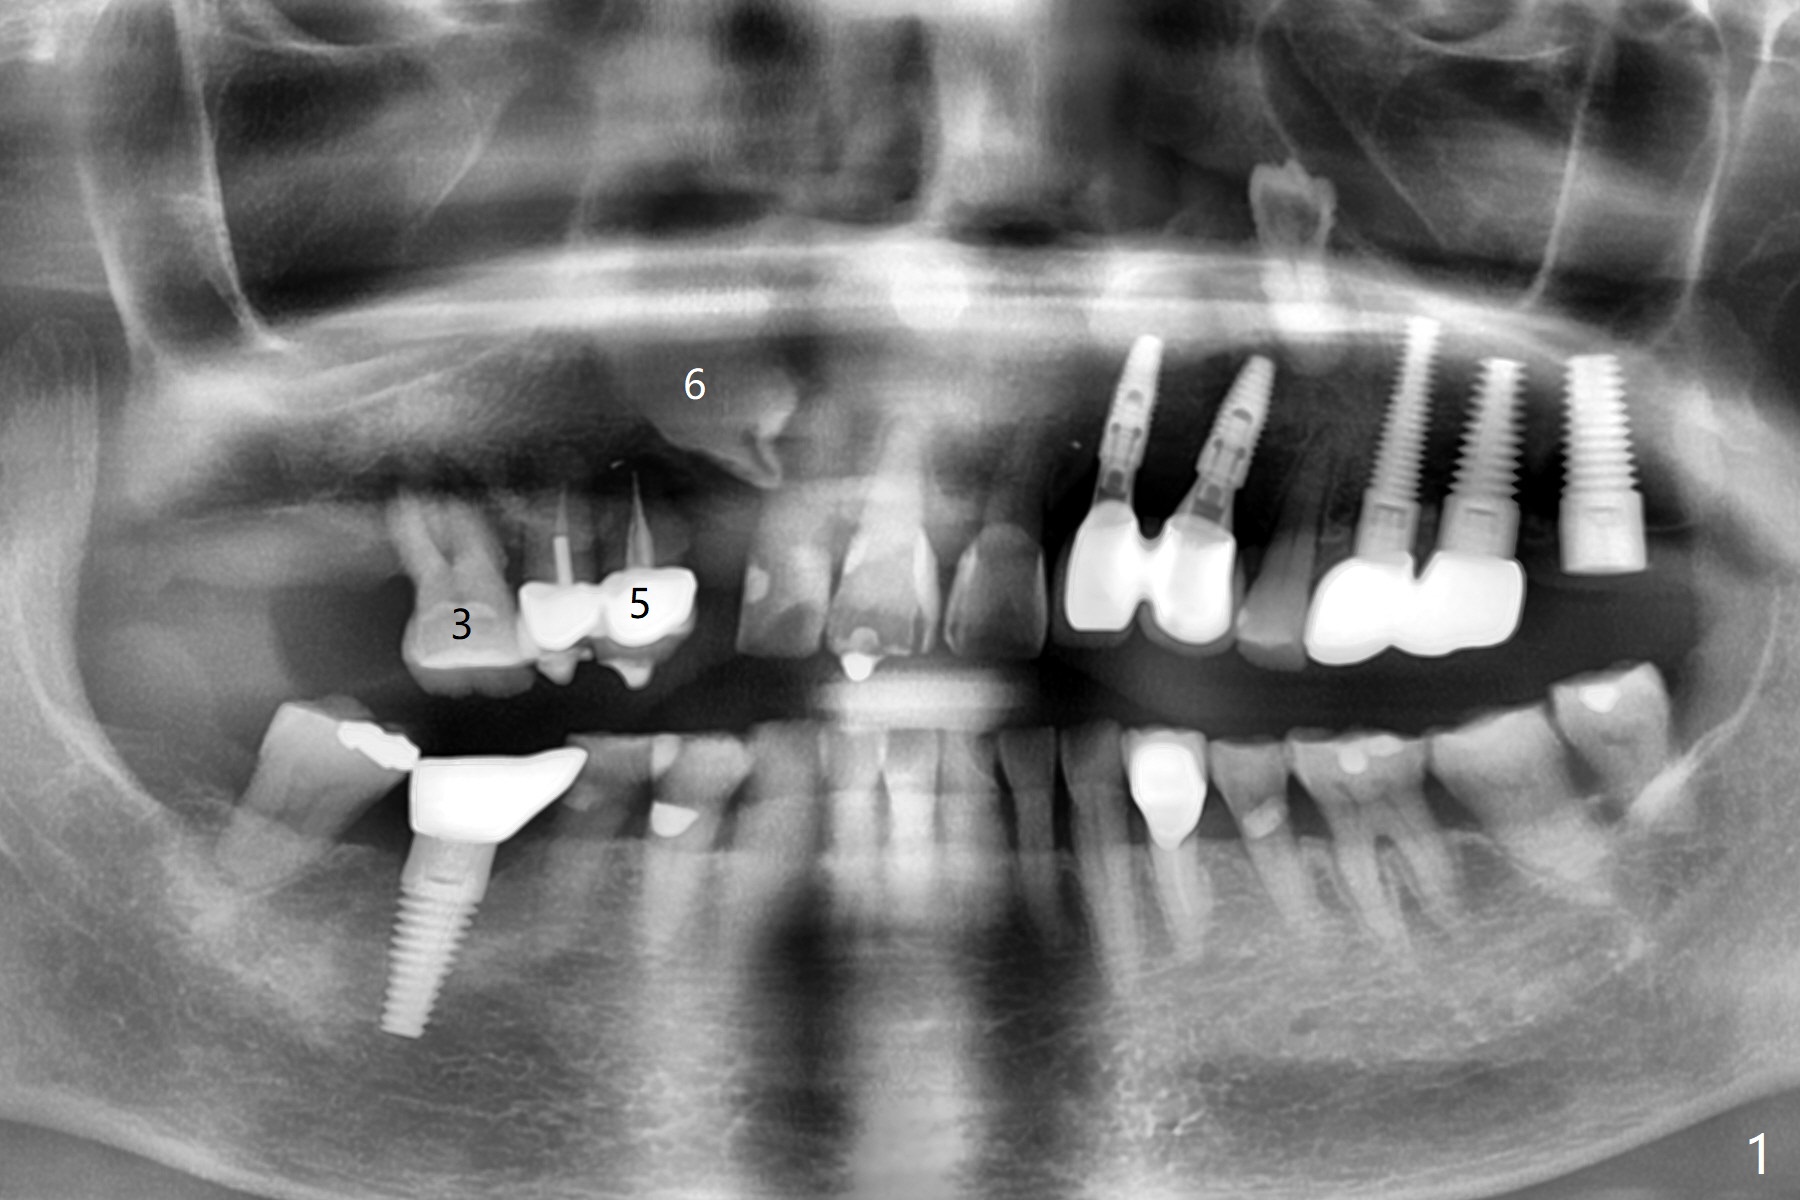

A 70-year-old woman requests implants at #3 and 5 because of bone loss (Fig.1). Since the impacted tooth #6 crosses the trajectory of the implant at #5, extraction of the former is necessary (Fig.2). Palatal bone loss is severe at #5, a 3.5x15 mm 1-piece implant will be placed slightly more buccal than what is shown for 4x13 mm 2-piece one at Fig.2. A 5x11.5 mm implant will be placed at #3 without sinus lift (Fig.3). In fact the patient is concerned about cleasenability of the cantilever bridge. One-piece implant will be placed if needed (Fig.4).